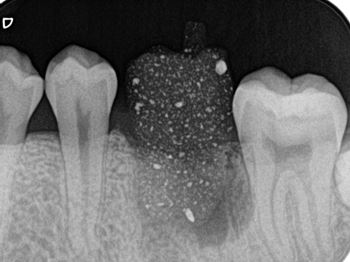

口腔外時間短縮と歯根膜温存を意識した術式:症例1-4

X線にて移植床形成量を確認